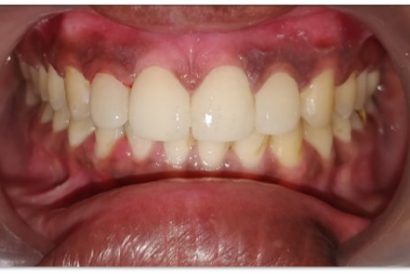

Patient Name: Sakshi Talwar

Tooth Number: 11

Diagnosis : fractured restoration

Treatment : Endodontic Treatment With 11 and fiber post and core, gingvectomy and frinectomy with 11

Restoration: Bonded Lithium Disilicate Emax Restoration